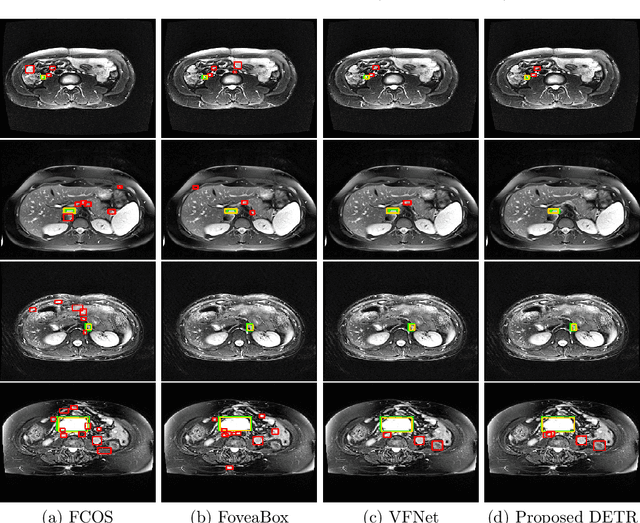

Abstract:Purpose: Identification of abdominal Lymph Nodes (LN) that are suspicious for metastasis in T2 Magnetic Resonance Imaging (MRI) scans is critical for staging of lymphoproliferative diseases. Prior work on LN detection has been limited to specific anatomical regions of the body (pelvis, rectum) in single MR slices. Therefore, the development of a universal approach to detect LN in full T2 MRI volumes is highly desirable. Methods: In this study, a Computer Aided Detection (CAD) pipeline to universally identify abdominal LN in volumetric T2 MRI using neural networks is proposed. First, we trained various neural network models for detecting LN: Faster RCNN with and without Hard Negative Example Mining (HNEM), FCOS, FoveaBox, VFNet, and Detection Transformer (DETR). Next, we show that the state-of-the-art (SOTA) VFNet model with Adaptive Training Sample Selection (ATSS) outperforms Faster RCNN with HNEM. Finally, we ensembled models that surpassed a 45% mAP threshold. We found that the VFNet model and one-stage model ensemble can be interchangeably used in the CAD pipeline. Results: Experiments on 122 test T2 MRI volumes revealed that VFNet achieved a 51.1% mAP and 78.7% recall at 4 false positives (FP) per volume, while the one-stage model ensemble achieved a mAP of 52.3% and sensitivity of 78.7% at 4FP. Conclusion: Our contribution is a CAD pipeline that detects LN in T2 MRI volumes, resulting in a sensitivity improvement of $\sim$14 points over the current SOTA method for LN detection (sensitivity of 78.7% at 4 FP vs. 64.6% at 5 FP per volume).

Abstract:Identification of lymph nodes (LN) in T2 Magnetic Resonance Imaging (MRI) is an important step performed by radiologists during the assessment of lymphoproliferative diseases. The size of the nodes play a crucial role in their staging, and radiologists sometimes use an additional contrast sequence such as diffusion weighted imaging (DWI) for confirmation. However, lymph nodes have diverse appearances in T2 MRI scans, making it tough to stage for metastasis. Furthermore, radiologists often miss smaller metastatic lymph nodes over the course of a busy day. To deal with these issues, we propose to use the DEtection TRansformer (DETR) network to localize suspicious metastatic lymph nodes for staging in challenging T2 MRI scans acquired by different scanners and exam protocols. False positives (FP) were reduced through a bounding box fusion technique, and a precision of 65.41\% and sensitivity of 91.66\% at 4 FP per image was achieved. To the best of our knowledge, our results improve upon the current state-of-the-art for lymph node detection in T2 MRI scans.